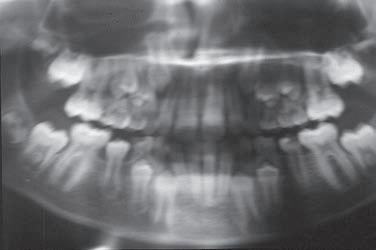

Jsem stále více přesvědčena o tom, že informaci o přítomnosti ortodontické anomálie, která se plně projeví až za několik let, máme k dispozici velmi brzy. Určitá podezření můžeme vyslovit obvykle už při zahájení první fáze výměny chrupu. Jen je třeba dobře se dívat a věnovat pozornost nenápadným symptomům, které na ni upozorňují. Jinak se budeme neustále setkávat s udivenými dospělými pacienty s retinovanými špičáky, s perzistujícími dočasnými zuby a s pacienty, jejichž chrup nelze kvůli ortodontické anomálii dobře ošetřovat.